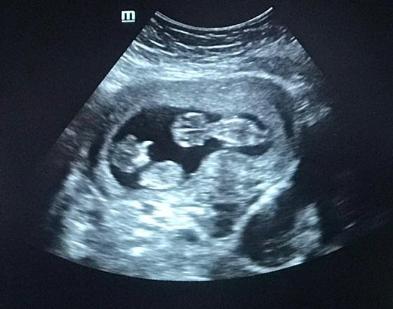

B超是女性早孕检查中必不可少的一项,但有的孕妈则会要担心,做B超会不会对身体不好?影响胎儿发育?特别是经阴道的B超。

其实,孕妈们的担心是多余的,在孕期做的B超,不管是腹部还是经阴道,对宝宝的来说其实则是安全的,是为了让医生对胎儿的状况做更准确的判断。

临床上的超声波探头发射强度小,超声波检查时间往往只有5—10分钟,对每个器官探测的时间更短。检查对胎宝宝危害极小,不会影响胎儿的正常发育。

判断胚胎位的位置,确定位于子宫内还是子宫外,排除宫外孕可能,若发生宫外孕,一旦孕囊破裂出血,很有可能危及孕妇的生命安全。

判断胚胎的大小是否与孕周相符,胚胎是否生长良好。如果发现孕囊中始终没有胎血管搏动、没有胚芽,说明这个胚胎可能已经停育了。

判断孕囊的数目,确定是单胎、多胎。因为双、多胎孕期的风险和妊娠期合并症比单胎增加很多,而绒毛膜性的不同,可导致其孕期的风险甚至最后分娩方式的选择都可能不同,所以早孕时的B超很重要。

B超还可看出子宫、双附件是否有异常。双子宫畸形、附件有包块、子宫肌瘤等都应在早孕时甚至孕前进行B超排查。